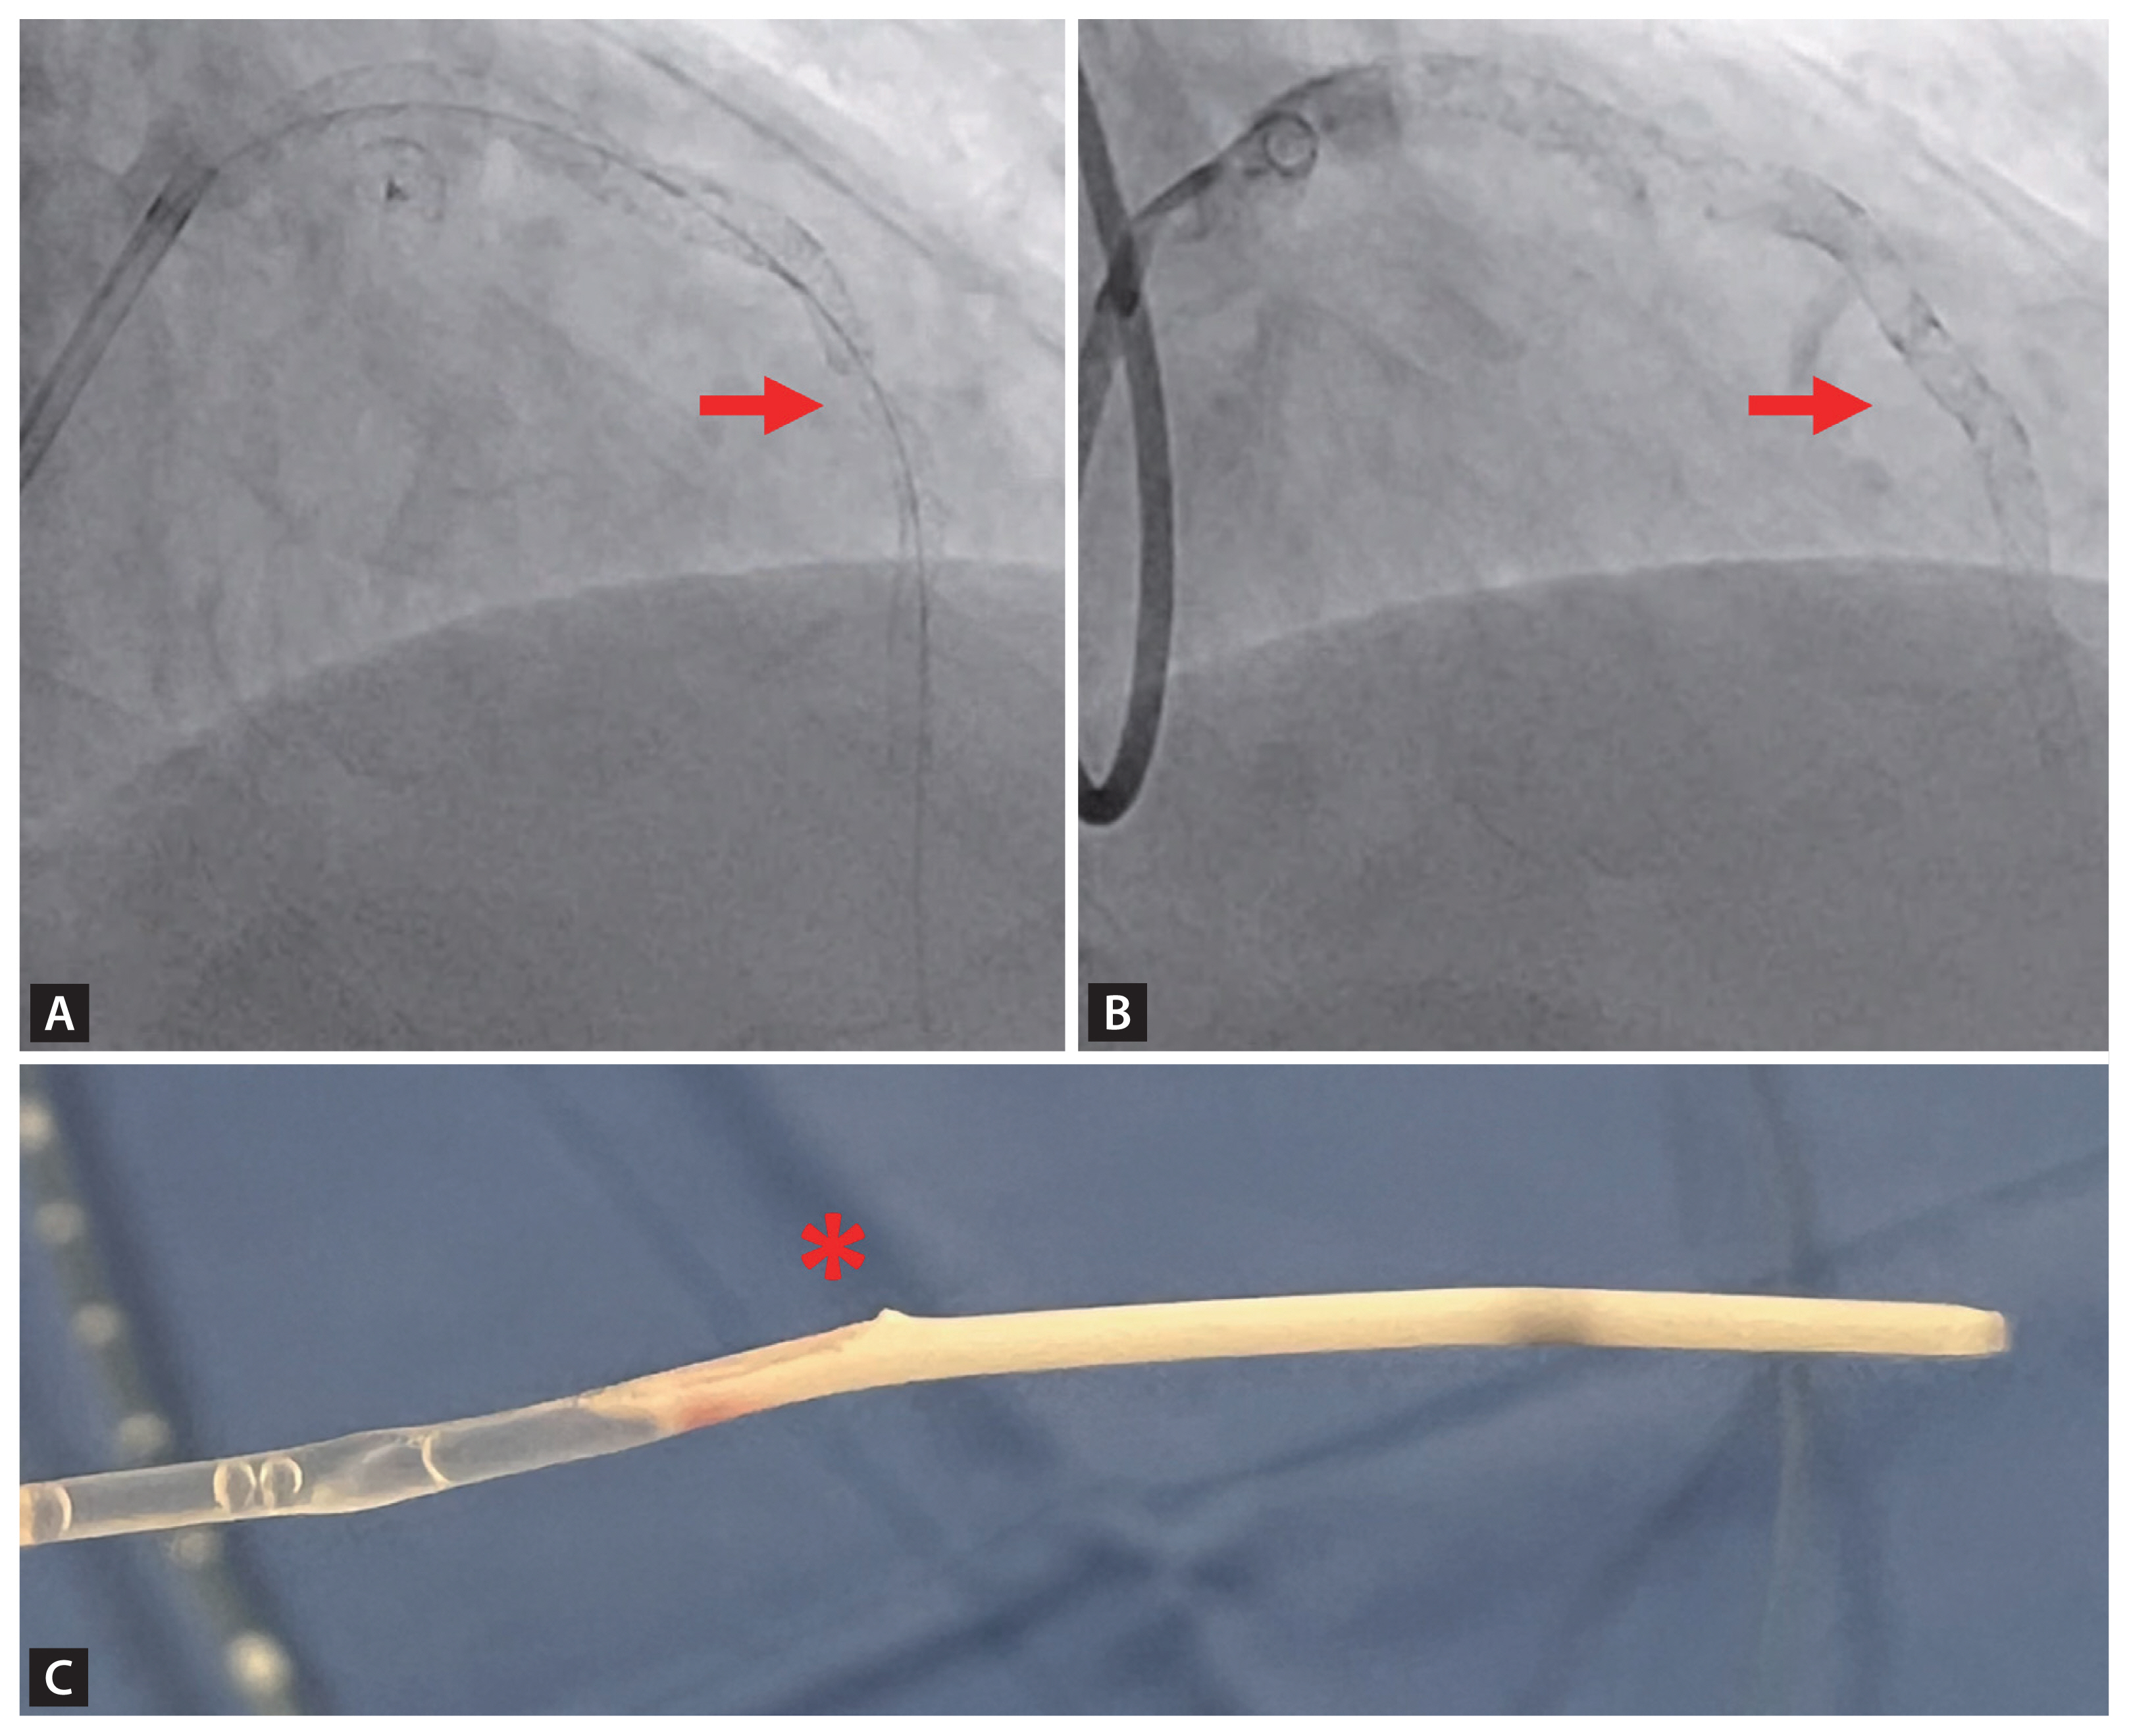

A 65-year-old male visited the emergency department and presented as anterior ST-elevation myocardial infarction (STEMI). Coronary angiography (CAG) showed severe stenosis (90%) in the proximal-to-mid segment of the left anterior descending artery as the culprit lesion. Despite severe tortuous the lesion, two drug-eluting stents (DES) (Synergy, 3.5 × 38 mm and 2.75 × 38 mm) were successfully implanted. Intravascular ultrasound (IVUS) was performed pre-optimization to assess stent apposition; however, catheter entrapment occurred at the proximal stent distal site during IVUS probe withdrawal. Forced extraction resulted in stent deformation with partial strut stripping, confirmed by repeat angiography. To address this complication, an additional stent (Synergy, 3.0 × 12 mm) was deployed (Fig. 1).

In both cases, catheter entrapment occurred at angulated stent segments within tortuous coronary anatomy during IVUS evaluation performed prior to post-dilation. The shared mechanism involved strut malapposition at bend points, where the IVUS catheter’s exit port became anchored between under-expanded struts. A critical divergence emerged in management:

Case 1: Forcible withdrawal induced stent deformation, necessitating additional stenting.

Catheter entrapment is a rare complication [1]. Major risk factors include stent under-expansion, tortuous anatomy, and small stent diameter [1]. Through these two cases, the importance of adequate post-dilation before IVUS assessment in PCI for small and tortuous lesions was underscored.